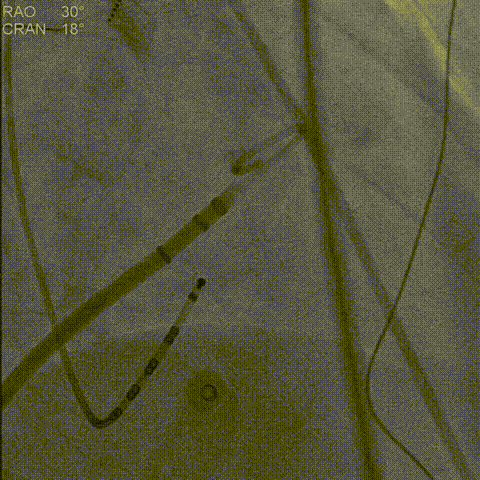

CHA2DS2-VASc评分3分,HAS-BLED评分4分,提示高卒中和出血风险,具有左心耳封堵手术适应症。团队实施左心耳封堵手术,术中DSA造影(RAO 30°+CRAN 20°、RAO 30°+CAUD 20°角度)显示上缘有少量残余分流,团队认识到DSA实时测量值小于CTA测量值,果断调整策略,更换为2430型封堵器。重新释放后,牵拉试验锚定牢固,肝位和右肩位造影显示上下缘无残余分流,封堵效果满意。此例充分体现了术者根据术中实际情况灵活调整的能力和LAMax封堵器多型号选择的优势。

右肩位左心耳造影测量锚定区:17.9mm开口部:21.5mm。

右肩位造影

右肩位造影上缘有微量残余分流

肝位左心耳造影测量锚定区:18.9mm,开口部:23.9mm。选择LAMax LAAC® 2127 Normal型号左心耳封堵器。

肝位造影

肝位造影上缘有少量残余分流

打开封堵伞后造影评估,考虑上缘有残余分流,且DSA测量小于CTA测量,更换大一号LAMax LAAC® 2430封堵器。